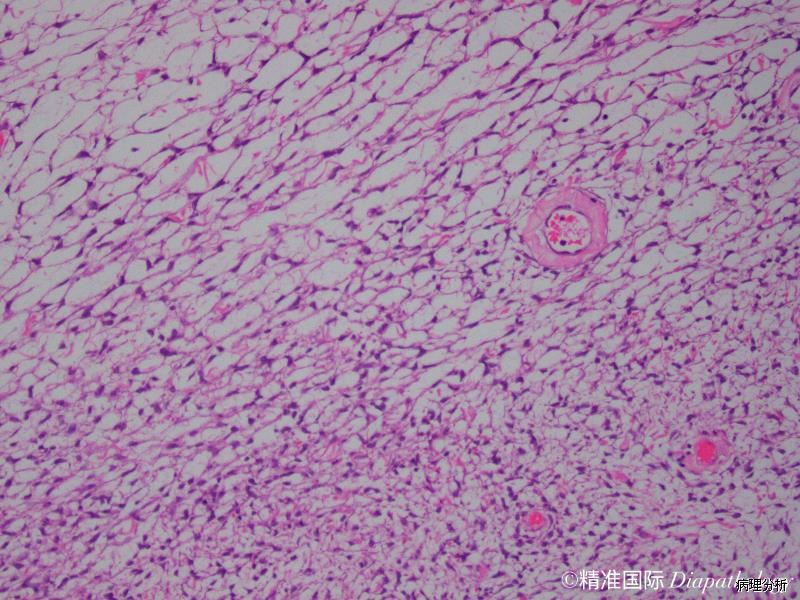

梭性细胞束交叉排列,常呈席纹状;

细胞密度不等,多数具中等细胞密度,无核异型,核分裂像少见,<4 个/10HPF;

常见带状胶原纤维或玻璃样变斑块;

弥漫细胞间水肿常见;